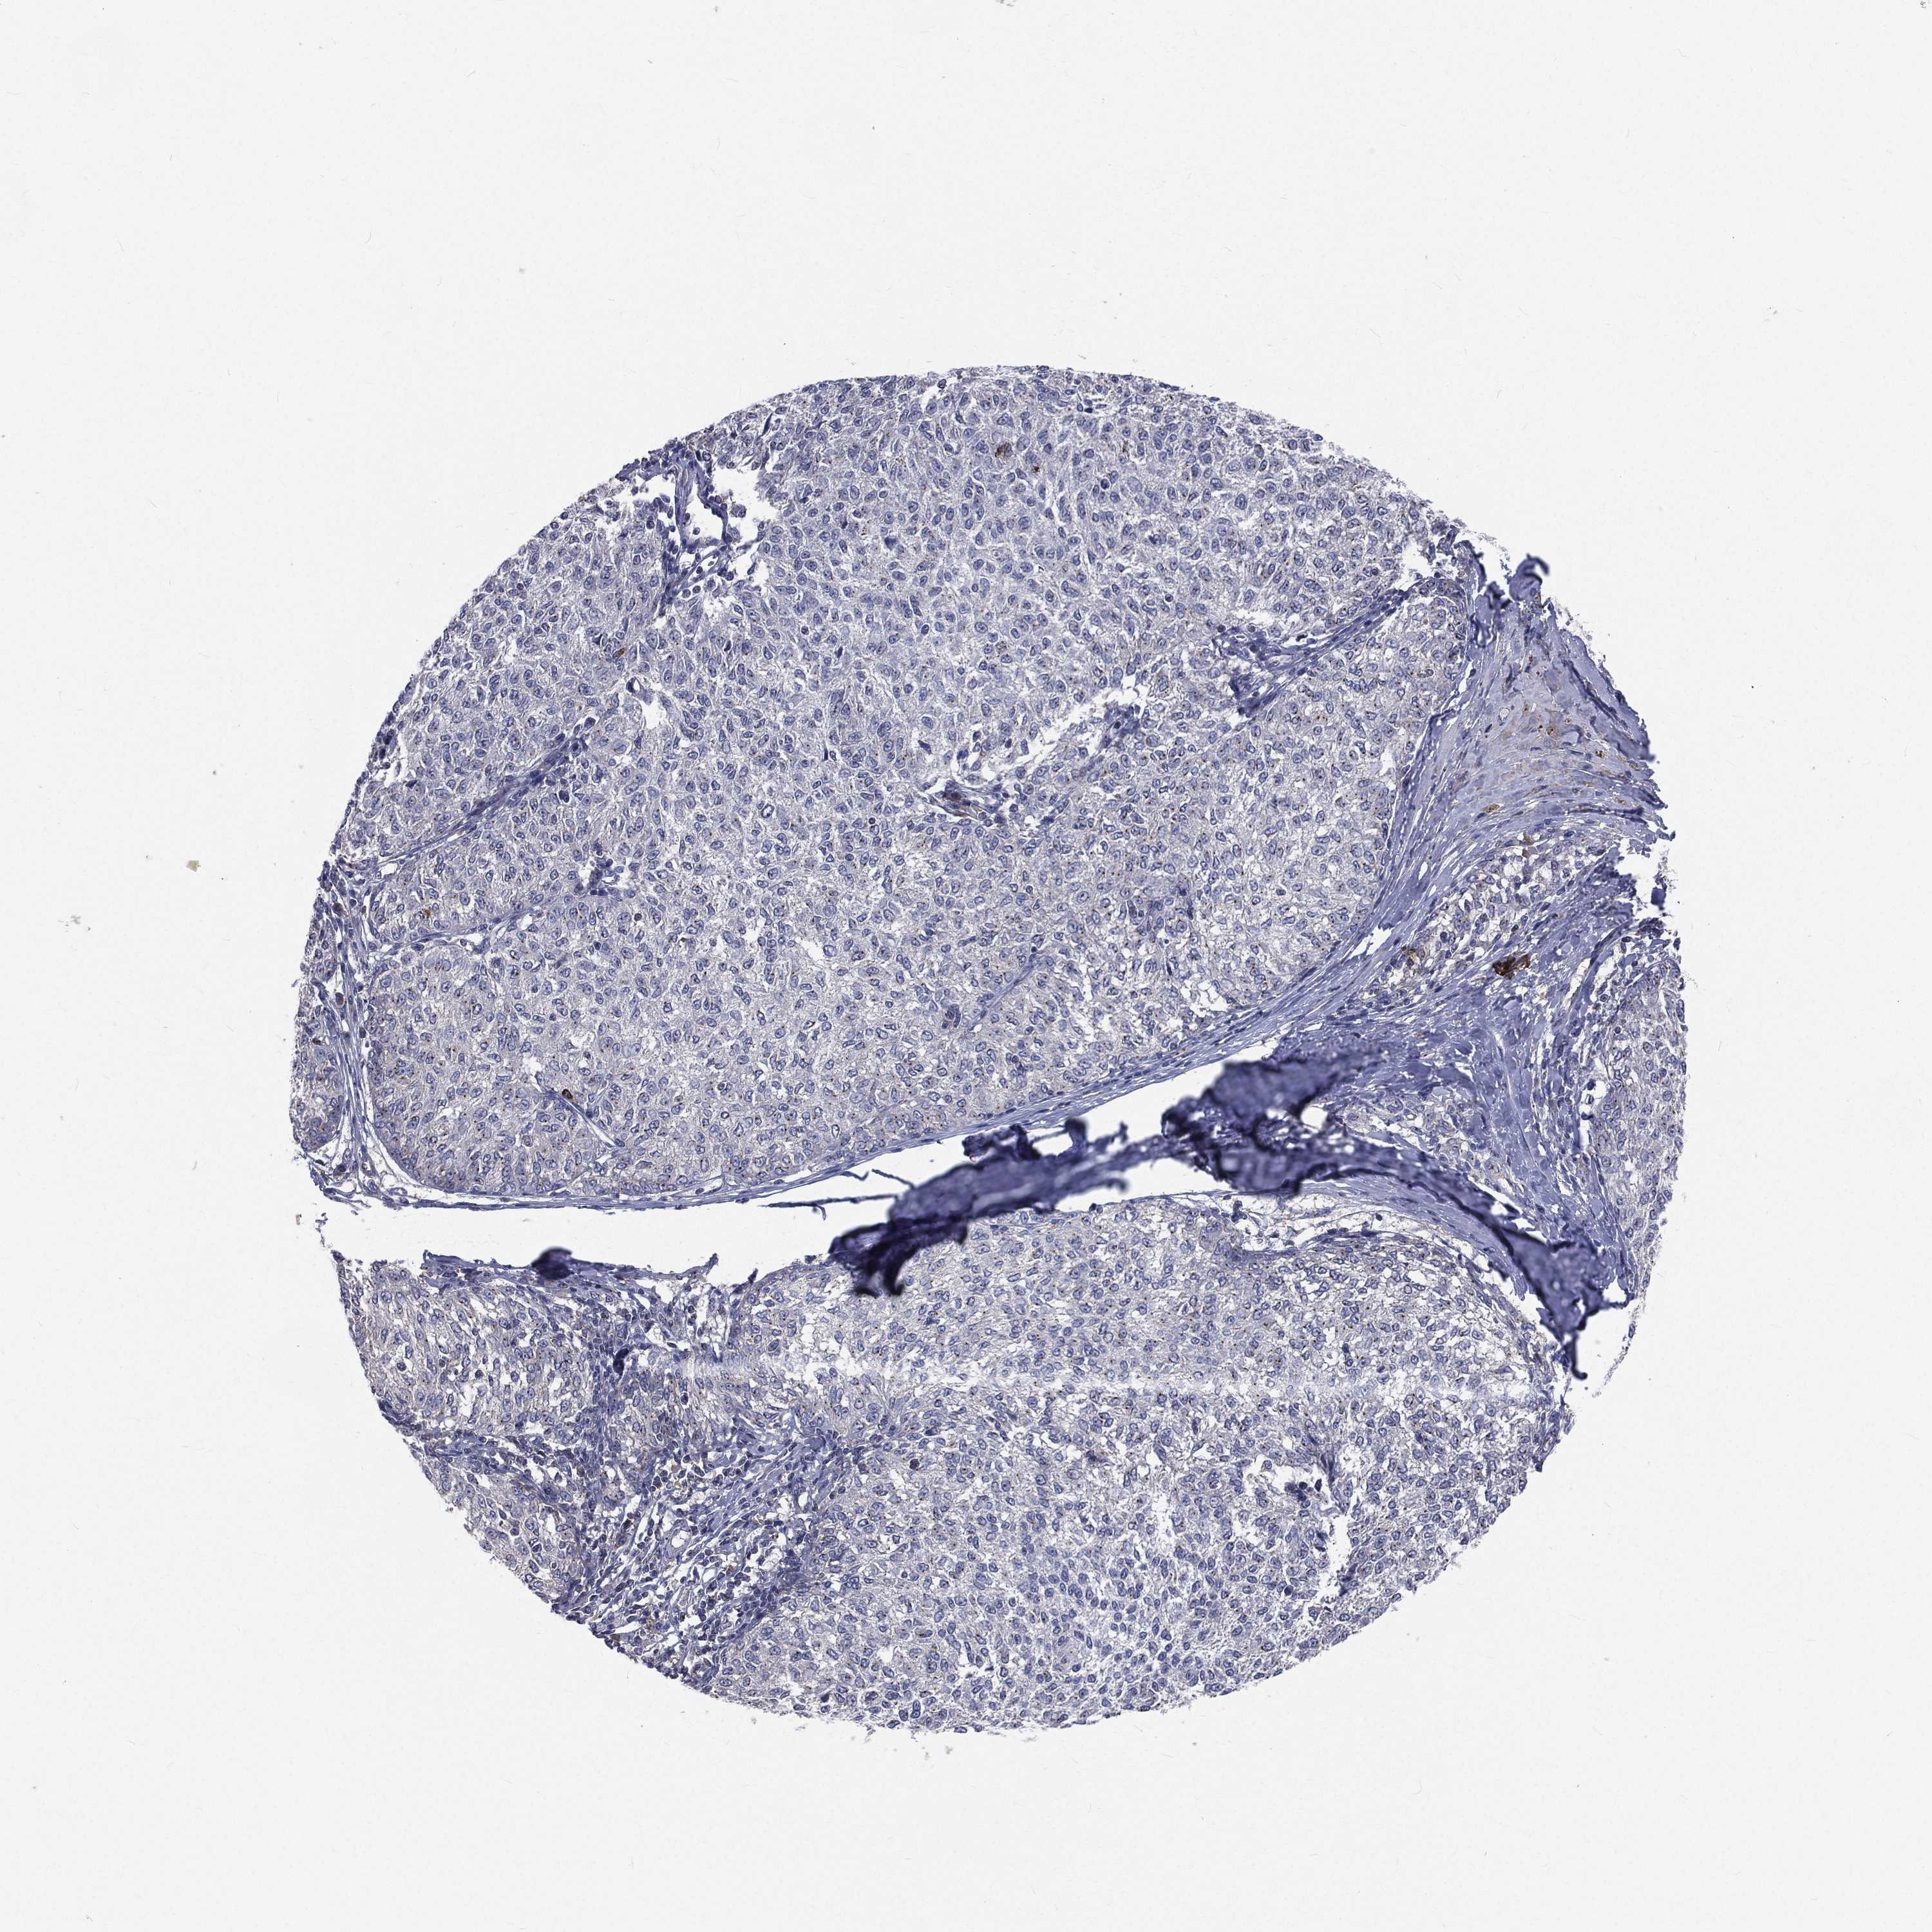

MELANOMA - Protein expressioni

A mouse-over function shows sample information and annotation data. Click on an image to view it in a full screen mode. Samples can be filtered based on level of antibody staining by selecting one or several of the following categories: high, medium, low and not detected. The assay and annotation is described here.

Note that samples used for immunohistochemistry by the Human Protein Atlas do not correspond to samples in the TCGA dataset.

Antibody stainingi

Antibody staining in the annotated cell types in the current human tissue is reported as not detected, low, medium, or high, based on conventional immunohistochemistry profiling in selected tissues. This score is based on the combination of the staining intensity and fraction of stained cells.

Each image is clickable and will lead to virtual microscopy that enables deeper exploration of all samples and also displays staining intensity scores, fraction scores and subcellular localization as well as patient and tissue information for each sample.

Antibody HPA021191

Antibody HPA021762

Malignant melanoma, NOS

Malignant melanoma, Metastatic site